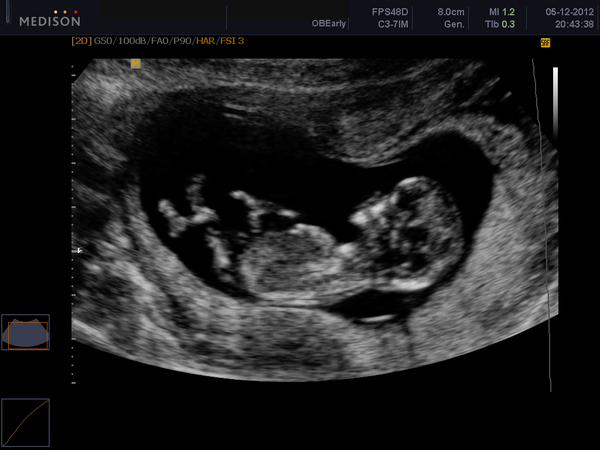

А малыш сначала был развернут к нам жопкой, но потом мы его разтормошили и он(она) сначала так сладенько смоктал пальчик, потом махал нам ручкой, ножками что-то там дрыгался, вобщем одно умиление. А вот и фотки:

А на этой фотке он(она) как попочкой к нам, как бы на горшочке сидит. И скажите или мне кажеться или там что-то посредине виднееться??

Что скажете??

. Ну как бы Вам обьяснить..

Короче он(она) развернута к нам попой и писей, сидит как-бы на горшочке, а дно горшочка "смотрит" на нас. Согнуты ножки, А посрединке, ближе к ножкам что-то виднееться беленькое продолговатое, небольшое такое. Ну что???